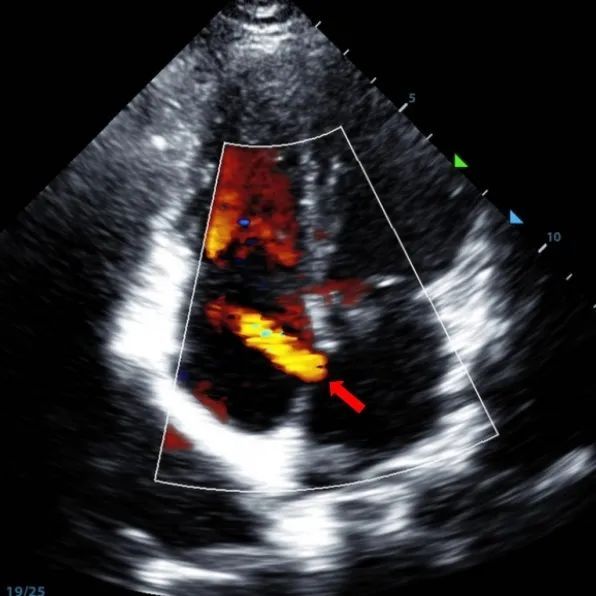

Laki-laki 9 tahun dengan secundum ASD (7.5-7.9mm) diperlakukan menggunakan MemoSorb BDASD-I 12mm occluber dan sistem pengiriman 12F. Tidak ada penyakit komplikasi atau komposit, pra-prosedur.

Serial echocardiographic follow-ups showed stable device position and favorable cardiac remodeling. Gradual degradation confirmed the occluder's long-term safety and efficacy.